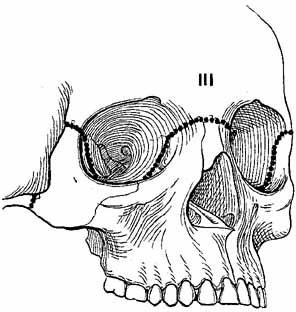

Complex orbital fractures include LeFort, naso–orbital–ethmoidal, zygomatic–maxillary–complex (ZMC or trimalar) and rim fractures. Generally, these fractures are repaired with a multidisciplinary approach provided by plastic surgeons, otolaryngologists, or maxillofacial surgeons. Fractures of the zygoma usually produce a ZMC fracture at three articulation sites: the frontozygomatic suture, the zygomaticotemporal suture, and the zygomaticomaxillary suture. The fracture may cause palpable step-offs of the orbital rim, flattening of the malar eminence, inferior displacement of the lateral canthus, and enophthalmos. The LeFort I (Guerin's) fracture occurs horizontally across the maxilla at the base of the nasal septum, is caused by trauma to the lower midface, results in malocclusion, and does not involve the orbit. The LeFort II (pyramidal) fracture extends from the nasofrontal suture along the nasal bridge to the medial wall at the level of the cribriform plate, posteriorly onto the orbital floor, and through the maxillary sinus (Fig. 14). This fracture results from trauma to the anterior mid-face, which causes a disarticulation of the body of the maxilla and mid-face from the zygomatic arch and cranium. In these injuries, the mid-face often has a sunk-in appearance.61 Epistaxis is a common associated finding. The more ominous cerebrospinal fluid rhinorrhea also occurs frequently, and it requires consultation of a neurosurgeon. A palpable inferior orbital rim step-off may be associated with infraorbital hypesthesia. Optic nerve trauma must be suspected. The globe may be enophthalmic and vertically displaced, and it may demonstrate extraocular motility disturbances.

Fig. 14 LeFort II fracture. (From Iliff NT: The ophthalmic implications of the correction of late enophthalmos following severe midfacial trauma. Trans Am Ophthalmol Soc 89:477–548, 1991)

The LeFort III fracture (craniofacial dysjunction) is a disarticulation of the facial skeleton from the base of the skull (Fig. 15). The fracture extends from the nasofrontal suture to the medial orbital wall at the level of the cribriform plate, along the orbital floor, following the inferior border of the greater wing of the sphenoid, and across the lateral wall, through the zygomatic arch and pterygoid plates. Because of the more posterior extent of this fracture, structures in the optic foramen and superior orbital fissure are highly susceptible to injury.

Fig. 15 LeFort III fracture. (From Iliff NT: The ophthalmic implications of the correction of late enophthalmos following severe midfacial trauma. Trans Am Ophthalmol Soc 89:477–548, 1991)